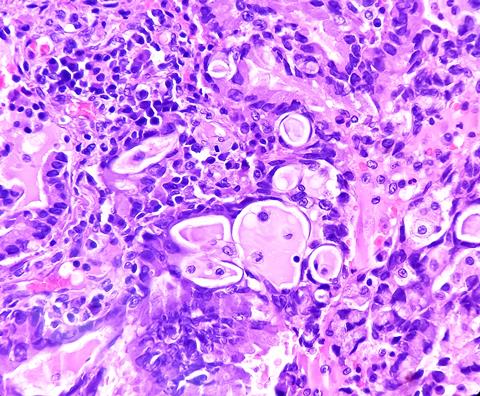

EGFR-driven lung adenocarcinoma does not respond to modern immunotherapies and although some drugs exist to treat it, patients usually develop a resistance to them within a few years. Macrophages are lung-resident immune cells designed to dispose of diseased and damaged cells and maintain a balance of protective lipids around lung alveoli. Lung adenocarcinoma uses macrophages, pulling them into the tumour microenvironment (TME) and altering their lipid metabolism. Then, the newly energised tumour cells cause further macrophage proliferation to supply more fuel.

Alveoli health relies upon a lipid-rich environment created by alveolar cells and sustained by macrophages. Maintaining the lipid balance becomes more complicated when tumour cells begin to exploit lipids to help themselves grow. Therefore, a greater understanding of the mechanisms macrophages use to regulate their metabolism and lipid production can offer insight into how tumour cells manipulate those mechanisms.

Dr Alexandra Kuhlmann-Hogan, first author, former postdoctoral researcher in Dr Kaech’s lab and current postdoctoral researcher at UCLA, elucidated: “The tumour cells excrete even more of a growth factor called GM-CSF (granulocyte macrophage colony-stimulating factor), which then causes the macrophages to grow alongside them and change their metabolism, resulting in excess lipids that the tumour cells use to strengthen themselves…The cancer was effectively hijacking this normal macrophage process of maintaining the lungs with healthy lipids in order to fuel itself.”

When the EGFR-driven lung adenocarcinoma cells secreted GM-CSF, it stimulated a gene in the macrophages named peroxisome proliferator-activated receptor gamma (PPARγ) which initiated their metabolic reprogramming and subsequent secretion of lipids. Also, the tumour cells use the lipids to power the continued activation of the EGFR-drive that helps the cancer grow.